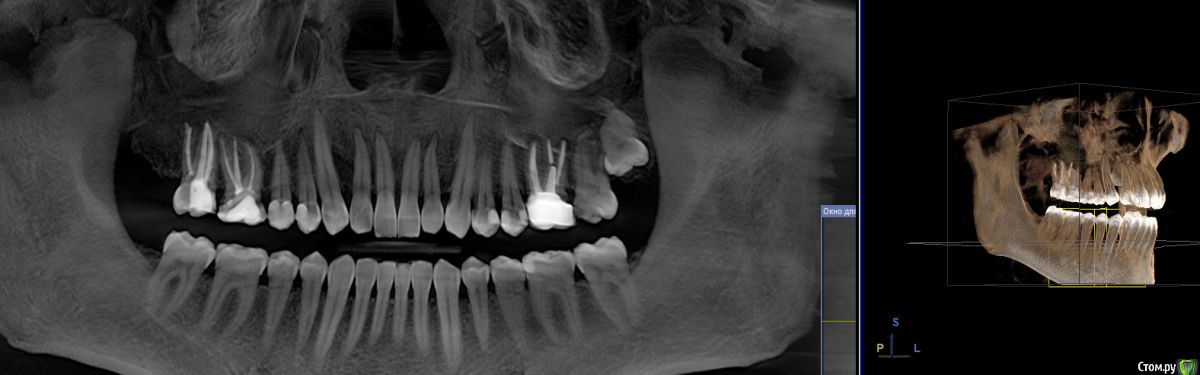

shamman Опубликовано 15 сентября, 2018 Поделиться Опубликовано 15 сентября, 2018 (изменено) Как вы понимаете, лечение в частных клиниках сейчас довольно дорогое. И меньше всего хотелось бы тратить деньги на процедуры которые не показаны. Сложилась ситуация недавно, хочу получить ваш совет. Это такая форма продажи ненужны услуг, или и правда так бывает? 1.Сходил на профессиональную чистку к гигиенисту. После процедуры она мне сказала, что у меня есть парадонтологические карманы по 5 мм, и что надо обязательно идти к парадонтологу. Я удивился, потому что ранее никогда ничего такого не бывало ни разу после гигиены. 2.Пришёл к направленному парадонтологу, доктор посмотрел и сказал, что кармы до 3 мм, и лечение не требуется. Но после сделанного КТ, сказала, что кое где остались камни судя по КТ. И надо бы к ней придти дочистить. Хм...я так понял, что кое-где чуть-чуть. Удивился, что врачи "путаются в показаниях". 3.Пришёл на эту процедуру, по факту мне обработали почти все дёсна ультразвуком, потом несколько зубов сделали закрытый кюретаж(вроде так называется, когда вручную скребу около десён спец. инструментом). Отполировали. По факту сказали, что раз в год надо у парадонтолога наблюдаться. По стоимости получилось ощутимо, в чеке написано что-то типа: "парадонтологическая гигиена". Я вот думаю, насколько мне была показана эта процедура? Или клиника таким образом обеспечивает загрузку парадонтолога? По факту, хуже от этой процедуры не будет, но вдруг она для меня была и не обязательна? Деньги-то потрачены...с учётом проф.гигены и парадонтологической существенная сумма. Вообще, может подскажите, что в таких случаях делать, перепроверять направление в государственной клинике, или другой? Расходы на эти процедуры существенные. Возможно как-то оптимально лечиться, только по показаниям? Снимок на всякий случай приложил, если это поможет. Изменено 15 сентября, 2018 пользователем shamman Ссылка на комментарий

St. Опубликовано 15 сентября, 2018 Поделиться Опубликовано 15 сентября, 2018 По снимку предрасположенность присутствует, но каких то очень критичных проблем с уровнем кости я не вижу. Наблюдаться раз в 6 мес стоит, и чистку по необходимости раз в 6-12 мес( зависит от уровня Вашей домашней гигиены). Где именно решать Вам, выбирайте доктора с которым будет комфортно и которому доверяете Ссылка на комментарий